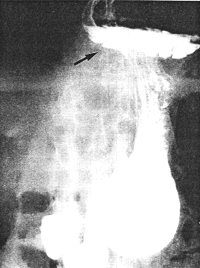

Case 32.2. A.G.C., female aged 64 years. Ten years previously a hiatus hernia had been diagnosed radiographically. At the present examination a large, sliding hiatus hernia with free gastro-oesophageal reflux was demonstrated in the Trendelenburg position (Fig. 32.2A). A constant contraction of the sphincteric cylinder, 5.0 cm in length, was seen (Fig. 32.2B). Its walls were smooth and regular, without evidence of local mucosal destruction, a niche, filling defect or other organic lesion. Emptying of fluid barium suspension was not delayed. At operation there was a hard, tumour-like contraction in the pyloric part of the stomach, extending proximally from the pyloric ring for a distance of 5.0 cm. The contraction was of such severity that the mass appeared avascular and greyish and at first simulated a carcinoma. However, gentle massaging caused it to relax, followed immediately by recurring contraction. A pylorosplasty was done at which the muscularis externa was seen to be three times the normal thickness. The mucosa bulged through the incision and the surgeon had no doubt that it was a case of adult hypertrophic pyloric stenosis (AHPS). There was no other local lesion. The hernia was repaired and a truncal vagotomy performed. Repeat radiological examination 7 months later showed a post-pyloroplasty appearance.

A![]() | |

B | |

| Fig. 32.2 A,B. Case A.G.C. Large, sliding hiatus hernia (black arrows). Contracted pyloric sphincteric cylinder (white arrows) | |